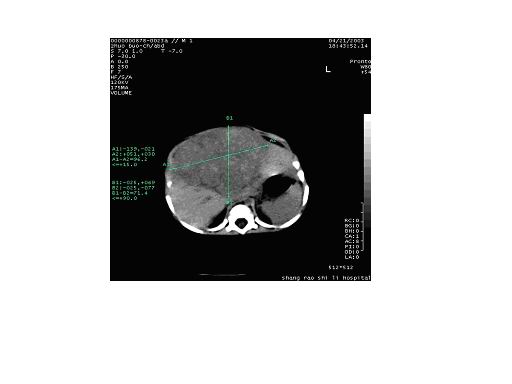

患者男性,10岁,腹痛4小时余,5年前患乙肝.查:右上腹压痛(+),反跳痛(+)血常规:wbs13.5x10(9)/l,b超提示:右肝实质性占位,性质待查.afp弱阳性患者男性,10岁,腹痛4小时余,5年前患乙肝.查:右上腹压痛(+),反跳痛(+)血常规:wbs13.5x10(9)/l,b超提示:右肝实质性占位,性质待查.afp弱阳性.

肝右叶巨大类圆形混杂密度影,边缘清晰,病变内部密度不均匀,可见环形钙化,我们考虑肝脏恶性肿瘤,肝母细胞瘤或肝细胞癌.请大家就平扫给予分析和指教.谢谢!!患者直接上省级医院检查,未做增强!

肝右叶见团块状混杂密度影,体积较大,密度不均匀,其内见低密度坏死区,并见点状、条状高密度钙化影,患者10岁,上腹痛,afp弱阳性,5年前患乙肝,首先考虑肝细胞癌,纤维板层样肝细胞癌不除外。增强扫描可鉴别,纤维板层样肝细胞癌,临床无特异性,以腹块和上腹部不适为主,无病毒性肝炎病史,实验室检查hbsag 阴性afp正常或略升高,ct表现病灶内出现钙化为其特点。